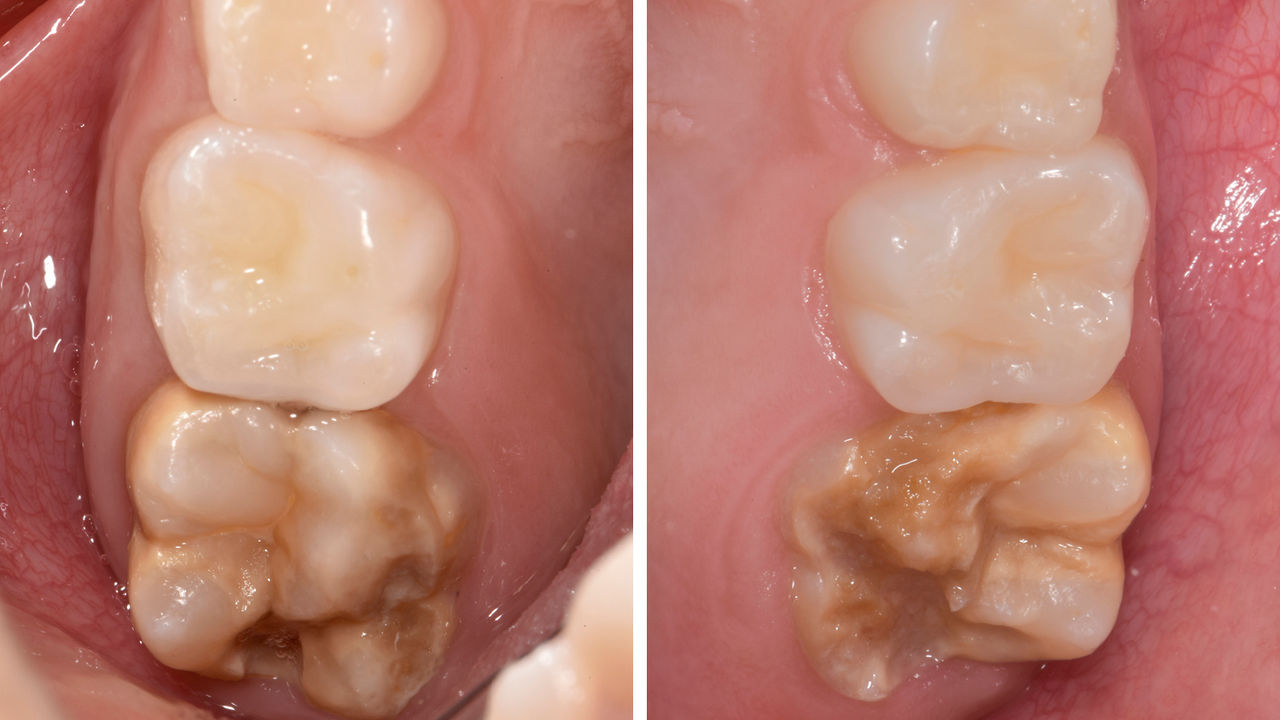

A lower second molar with sensitivity presented with cracks as well as an extensive Class I composite restoration on the buccal surface. According to the minimally invasive concept a CAD/CAM partial crown was planned, fabricated and bonded using CEREC Tessera in a single visit.

Before: Failed amalgam restoration needing replacement. Patient complaining of sensitivity and tooth presenting multiple cracks.

After: Chairside CAD/CAM partial crown restoration fabricated with CEREC Tessera Advanced Lithium-Disilicate glass ceramic.